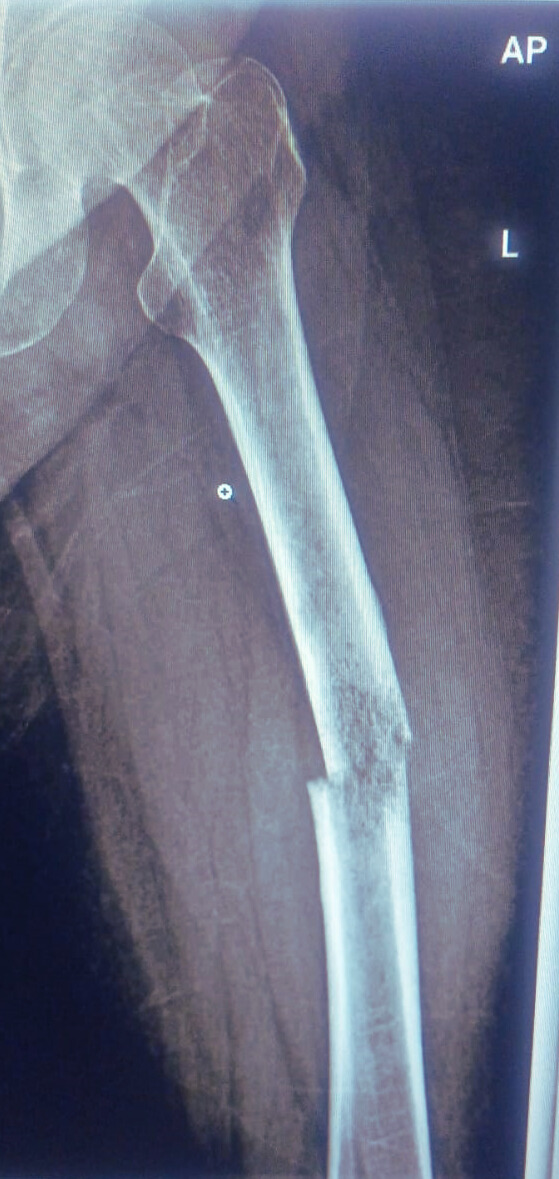

Preoperative Findings:

X-ray revealing a clear diaphyseal transverse break